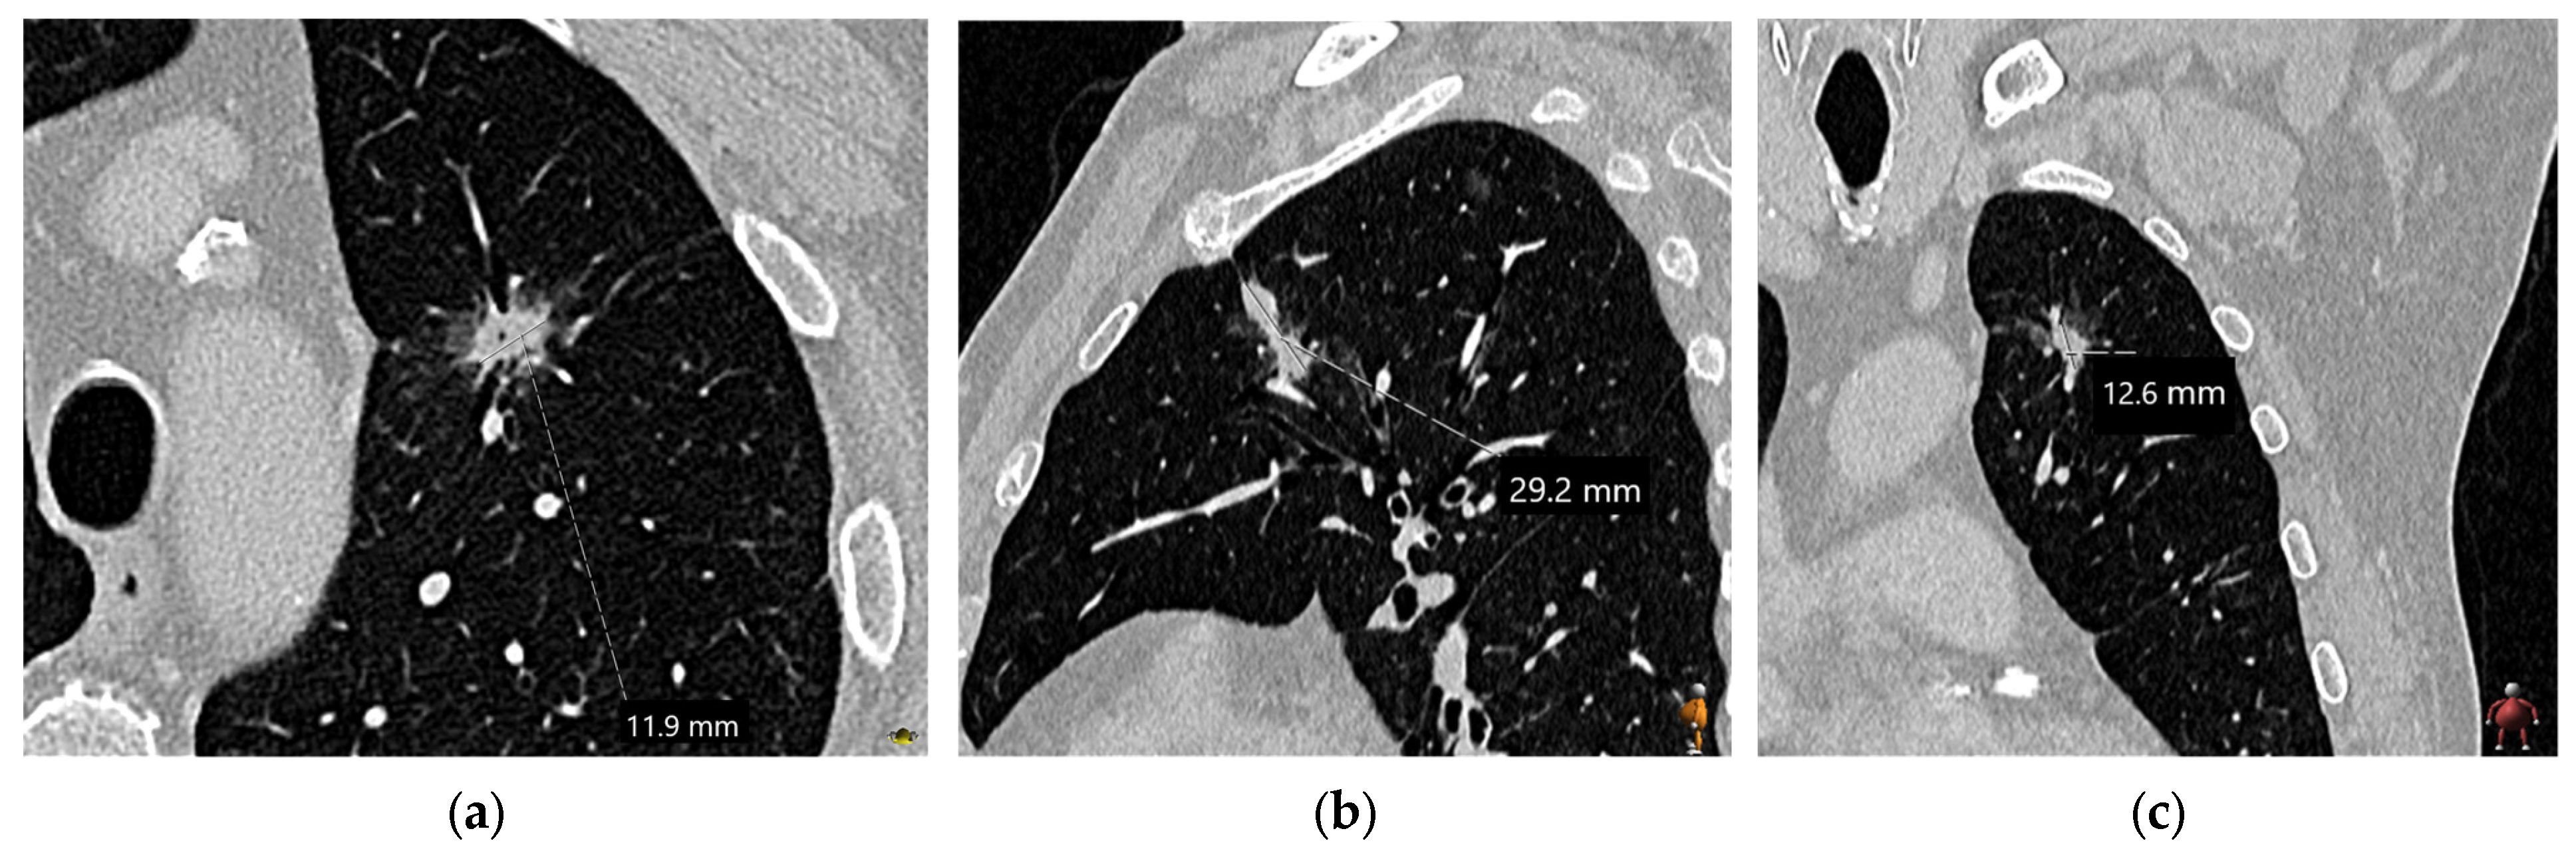

3.1. Tumor Size

| Slice thickness | Use contiguous thin sections (≤1 mm) |

| Measurement settings | Perform all measurements using a lung window setting (width 1500, level −600) with a sharp filter |

| Recording dimensions | Document nodule dimensions in centimeters, including millimeter increments |

| Solid and pure ground-glass nodules | Measure the maximum long-axis diameter in the axial, sagittal, and coronal planes |

| Part-solid nodules | Measure the maximum long-axis diameter of the nodule, including the ground-glass (GG) component, in the axial, sagittal, and coronal planes. Also, measure the maximum long-axis dimension of the largest solid component. Report both dimensions; however, for staging purposes, use only the largest solid component dimension |